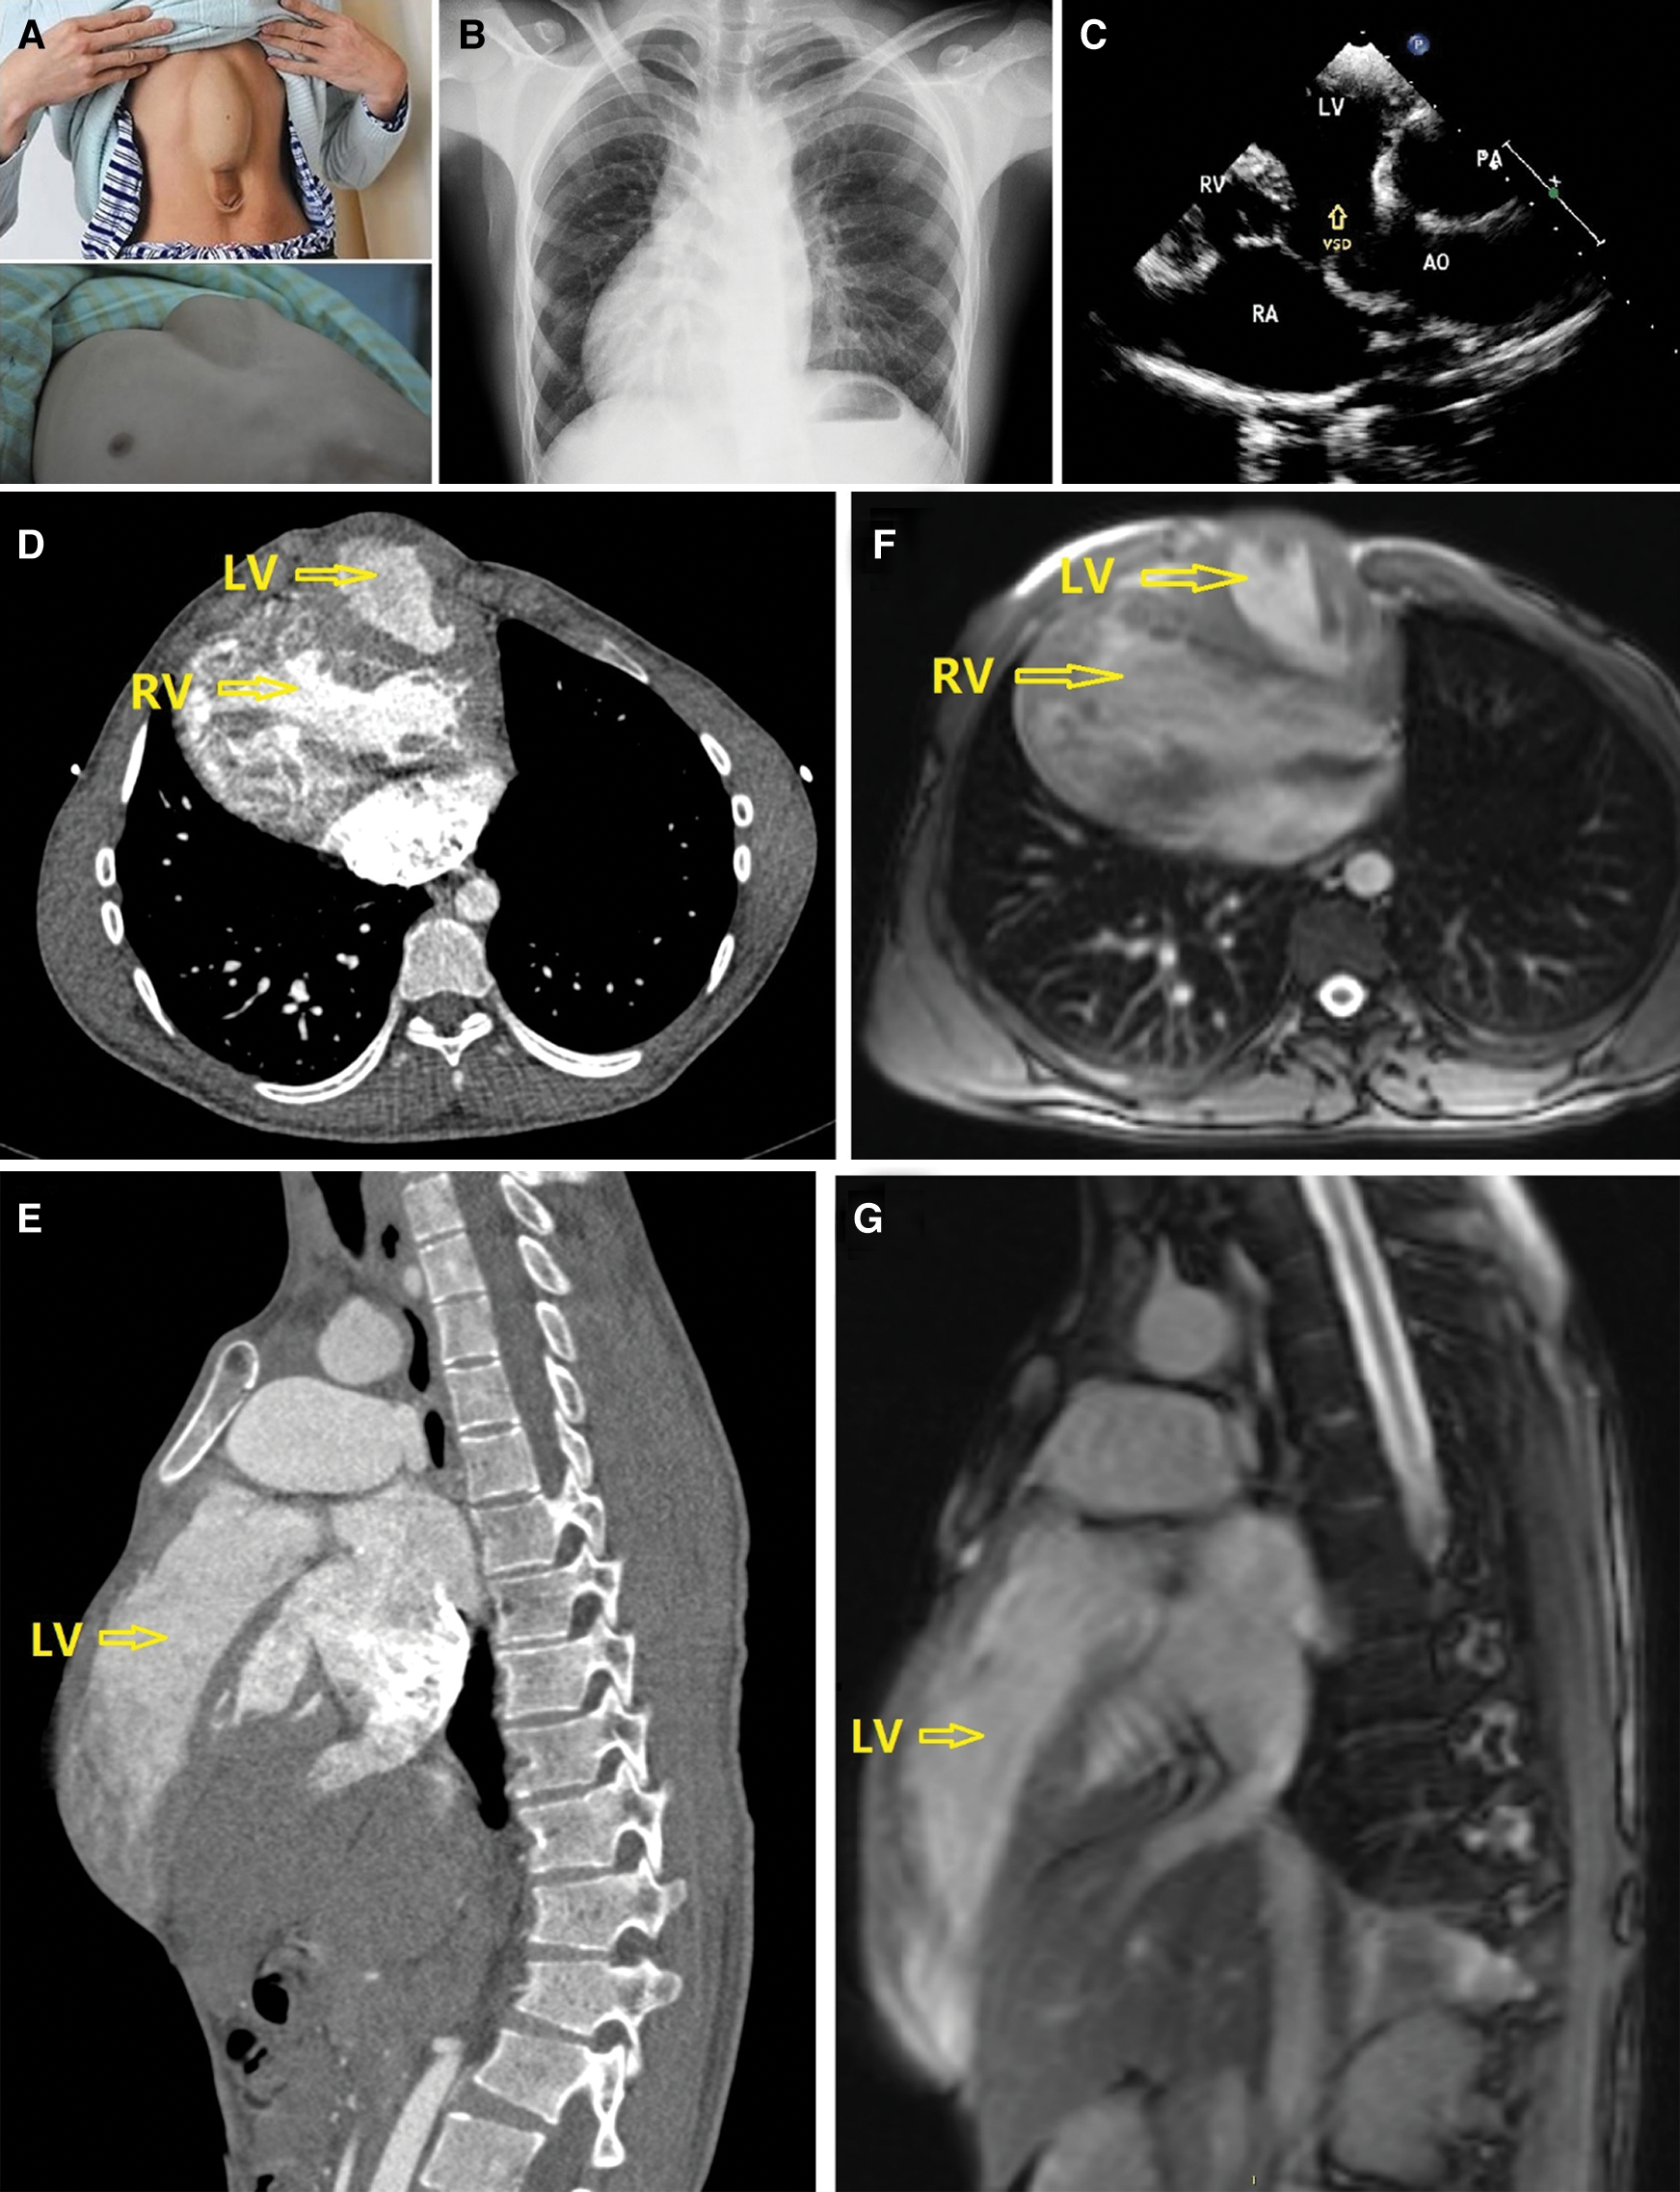

A 24-year-old male patient with a extrathoracic heart extending into supraumbilical abdominal wall (Fig. 1A) presented with symptoms of tachypnea, mild cyanosis and clubbing fingers. Physical examination showed a thoracoabdominal wall defect. The xyphoid was absent and the sternum was short. Oxygen saturation was 85%. 3/VI systolic murmur could be heard at the 2nd∼4th intercostal space near the right sternal border. Chest X-ray showed bilateral pulmonary congestion, dextroversion and enlarged right heart (Fig. 1B). The echocardiogram showed situs solitus, a 3.2 cm secundum atrial septal defect, functional single atrium, a 2.8 cm subaortic ventricular septal defect, double outlet right ventricle, overriding aorta with 80% of the aortic orifice over the right ventricle, and subpulmonary valve outflow tract stenosis (Fig. 1C).

Figure 1: (A) The extrathoracic heart. (B) Chest X-ray. (C) Echocardiogram. (D,E) CTA. (F,G): MRI. LV, left ventricle; RV, right ventricle; RA, right atrium; AO, aortic orifice; PA, pulmonary artery; VSD, ventricular septal defect

CTA and MRI showed a ventral thoracoabdominal wall defect with the two ventricles protruding through the defective of anterior diaphragm into epigastrium (Figs. 1D–1G). Double outlet right ventricle, subpulmonary valve outflow tract stenosis, and the diameter of systolic phase and diastolic phase are 0.5 cm and 1.5 cm. Diameter of pulmonary truncus are 3.4 cm, right pulmonary artery is 1.8 cm, left pulmonary artery are twist and diameter are 1.2 cm. Subaortic ventricular septal defect are 2.8 cm, secundum atrial septal defect are 3.2 cm.

The precise anatomic identification of the components of the pentalogy of Cantrell is extremely important for treatment planning and prognostication. Multimodality imaging with echocardiogram, CTA, and MRI remains helpful for pretreatment planning. Echocardiogram will lead to the diagnosis of the intracardiac anomalies. CTA and MRI were chosen for its capacity to demonstrate the segmental anatomy and the position of the heart relative to the bones of the thoracic cage. With the clinical presentation and multimodality imaging findings reported, we arrived at a diagnosis of class I pentalogy of Cantrell for this adult patient, which is very rare. The complex combination of the aforementioned cardiovascular anomalies suggested a poor prognosis.